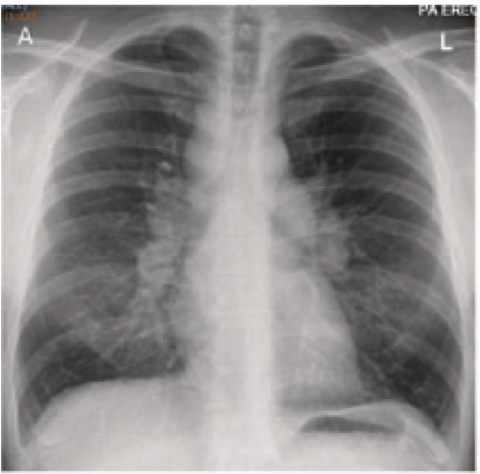

Antibiotic regimen of choice for this 42 year old female with dental caries admitted with 2 week H/O headache

What is ceftriaxone and metronidazole